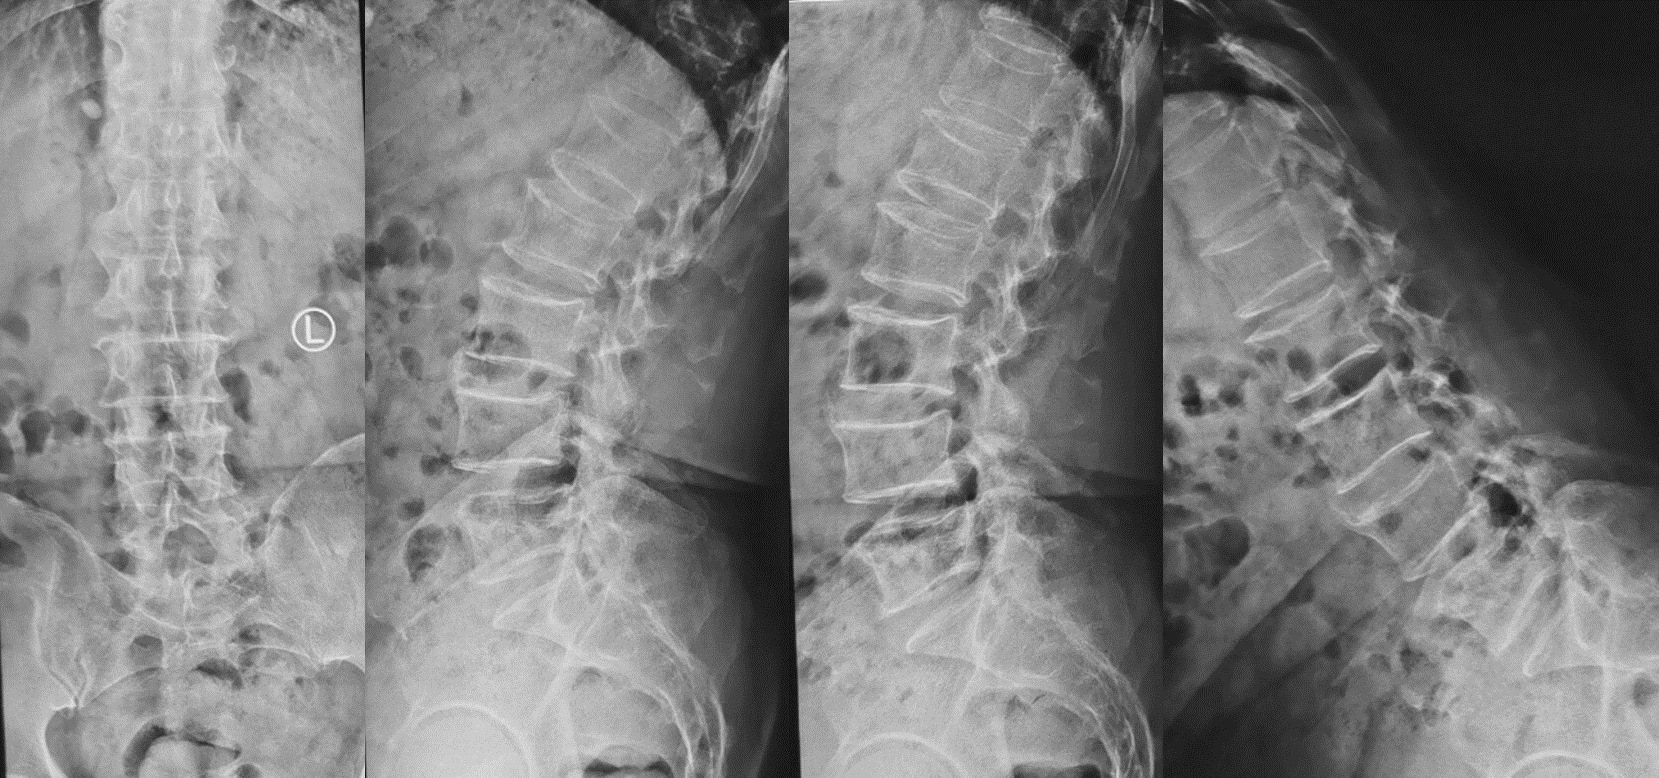

术前影像

第二例患者男性,67岁,患者因“腰痛并右下肢放射痛1年余,加重1月”入院,发病以来反复保守治疗,未好转,1月前症状加重,间歇性跛行,行走100米后因疼痛无法继续行走。入院后经术前讨论、评估,制定治疗方案,行OLIF手术。次日患者下地活动,下肢症状消失,疗效满意。

第三例51岁女性患者,因“右下肢放射性疼痛、麻木1年,加重1月余”入院,发病以来反复多次保守治疗无效。入院后经术前讨论、评估,制定治疗方案,行OLIF手术,该病例采用后路经皮椎弓根螺钉内固定。次日患者下地活动,下肢症状消失,疗效满意。